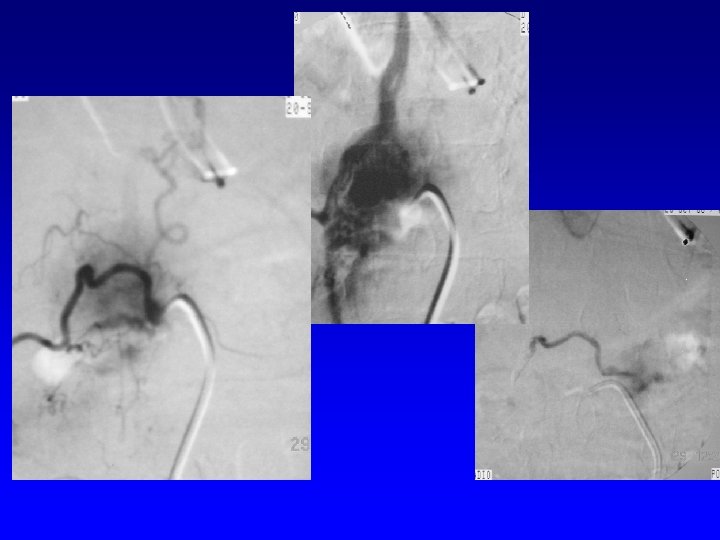

Fistule Durale AV • Artériographie – localisation précise de la fistule – cher 1 ou pls afférences artérielles – le plus souvent fistule postérolatérale – le plus souvent pas d ’artère médullaire conjointe

Fistule AV durale

Fistule AV durale • Embolisation: – injection d ’histoacryl après KT super sélectif de l ’a. radiculaire – occlure le segment initial de la veine – occlure la région de la fistule et la partie finale de l ’artère afférente – pas d ’occlusion de la veine ascendante de drainage ++++

Fistule AV durale Après E°

Fistule AV durale • Embolisation: – peut être faite pendant l ’A° Dc – Informer le patient – succès dans 70% des cas – risque de reperméabilisation chirurgie – morbidité faible